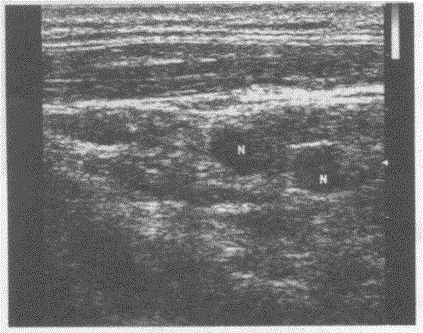

问题 临床资料:男,44岁,自述患慢性顽固性咽炎多年,久治不愈。 超声综合描述:右颈部可见数个长圆形低回声,边界清晰,形态规则。 超声提示:

选项 A.右颈部多发肿大淋巴结(慢性炎性肿大) B.右颈部淋巴结转移瘤 C.右颈部正常淋巴结声像图 D.右颈部淋巴结结核

答案 A